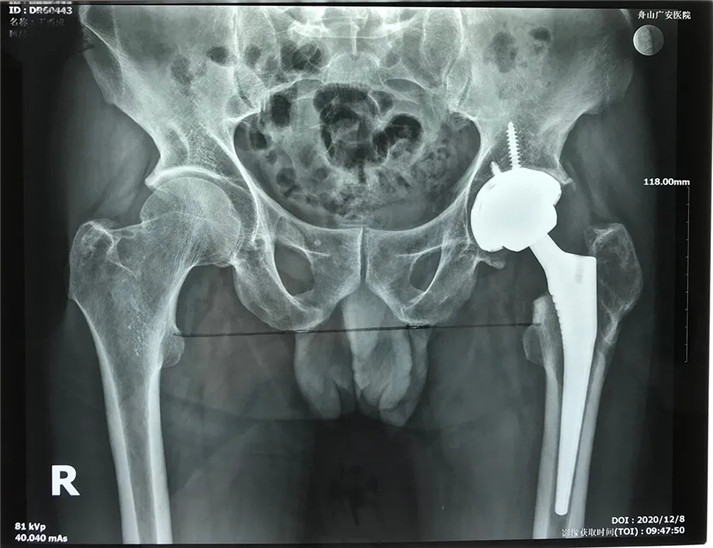

經(jīng)過周密的術(shù)前準(zhǔn)備,在身體符合手術(shù)指征后,丁大哥接受了全髖關(guān)節(jié)置換術(shù)。術(shù)中發(fā)現(xiàn)術(shù)前規(guī)劃產(chǎn)生的假體大小、位置、角度均非常理想,大大縮短了手術(shù)時間,全程十分順利。術(shù)后,丁先生恢復(fù)良好,次日即可下床活動。目前術(shù)后一個月,可以干活了。對于此次手術(shù),丁大哥及其家屬表示非常滿意。

術(shù)后